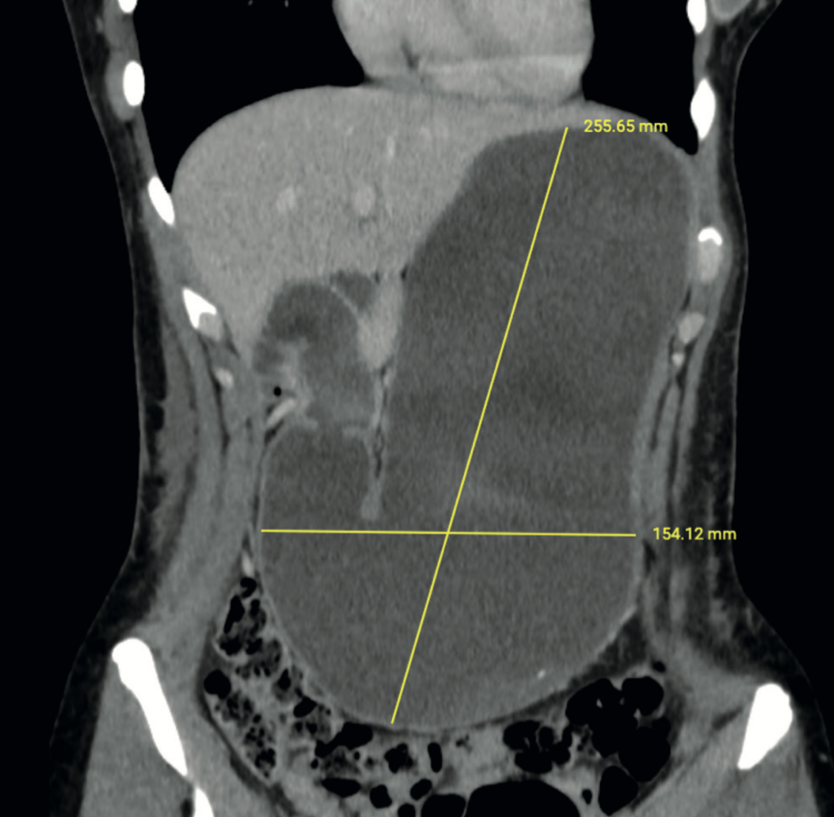

Gabriela Susana Ochoa Suazo, Nicolas Jarufe Cassis, Martin Dib Marambio

|

|

|